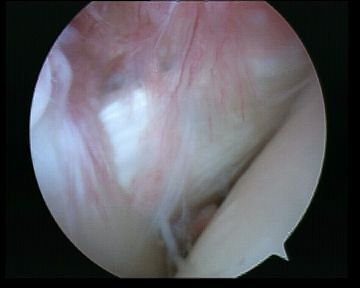

Subacromial space

Portals

| Posterior | Lateral subacromial portal |

|---|---|

|

Redirect posterior portal Under acromion |

Midportal clavicle |

| Usually viewing portal |

Rotator cuff repair / Subacromial decompression Distal clavicle resection |

![]() |